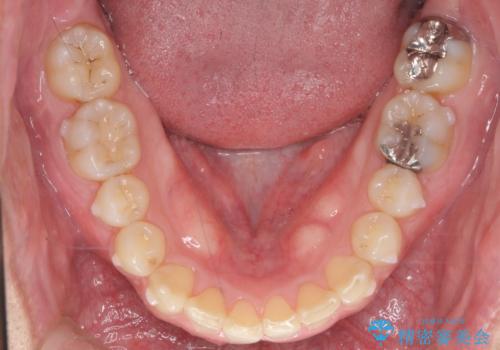

2級ディープバイト 遠心移動を伴うマウスピース矯正

・深い噛み合わせ(ディープバイト) ・2級性の咬合関係(上顎前突)・前歯のがたつき

深い噛み合わせと上顎前突の状態を治すのに時間がかかりましたが、治療後は理想的で安定した咬合関係となりました。